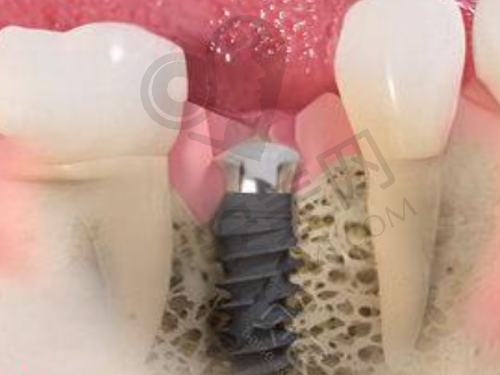

手术前,护士为我做了一些准备工作,如清洁口腔、消毒等。虽然医生已经跟我详细解释了手术过程,但我心里还是难免有些紧张。进入手术室后,医生再次跟我确认了手术方案,并安慰我不要紧张。手术开始了,医生先给我打了局部麻醉,整个过程中我并没有感觉到明显的疼痛。医生的操作非常熟练,每一个步骤都进行得特别精细。在种植体植入的过程中,我能感觉到医生在小心翼翼地操作,生怕对我的口腔造成任何损伤。整个手术过程大约持续了一个多小时,手术非常成功。术后,医生叮嘱我要注意休息,按照医嘱服用消炎药,并在规定的时间内来医院复诊。

经过几个月的愈合期,终于到了安装牙冠的阶段。这意味着我的门牙种植即将大功告成,我心里充满了期待。安装牙冠的过程相对简单,医生先对我的种植体进行了一些调整,然后为我选择了合适的牙冠。牙冠的颜色和形状都跟我的自然牙齿非常接近,几乎看不出是种植的牙齿。医生小心翼翼地将牙冠安装在种植体上,然后进行了一些微调,确保牙冠的位置和咬合都非常合适。安装完成后,我看着镜子里焕然一新的自己,心中充满了喜悦。我的门牙又修复了往日的美观,我终于可以自信地微笑和与人交流了。